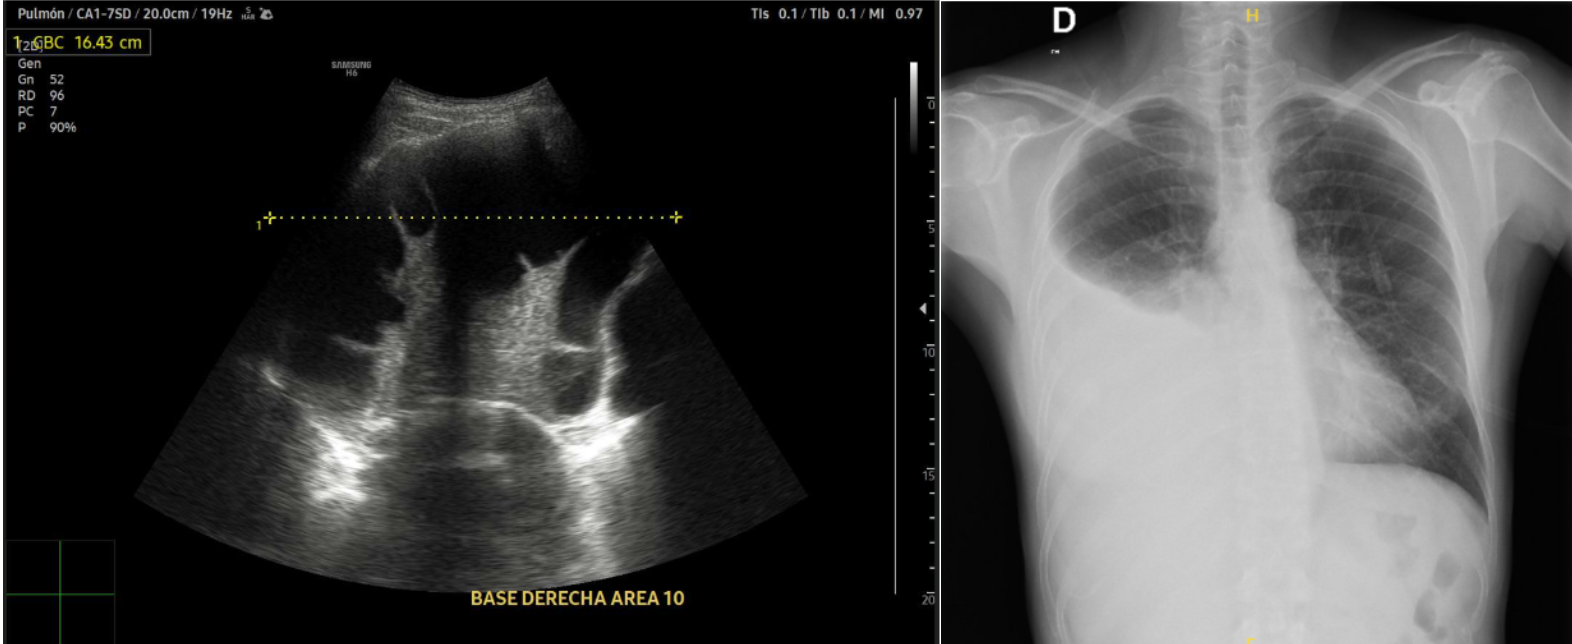

Realizamos Ecografía clínica pulmonar: imagen anecoica con septos finos y signo de la medusa compatible con derrame pleural tabicado con atelectasia en base derecha de aproximadamente 1150 ml por cuantificación de Goecke 2, en ápex líneas B finas. Campo pulmonar izquierdo líneas A.

En urgencias hospitalarias: Dímero D 1400 , sin leucocitosis, Radiografía de tórax derrame pleural derecho, Angiografía pulmonar: descarta TEP. Moderado/severo derrame pleural derecho con atelectasia pasiva.

Múltiples toracocentesis diagnósticas/evacuadoras total de 1,08 litros y con líquido pleural tipo exudado linfocítico; microbiología y citología negativa. Ecografía pulmonar control: persistencia de DP y aumento de tabicación. Tomografía abdomino pélvico confirma persistencia de derrame. Analítica destaca PCR y Procalcitonina elevadas. Nueva toraconcentésis ecodirigida: líquido pútrido, cultivo de DP: positiva para Parvimonas micra Fusobacterium nucleatum. Antígeno orina positivo: neumococo. Inicia Piperacilina/Tazobactam e inserción drenaje pleural con aspiración e instilación de urokinasa durante 10 días.